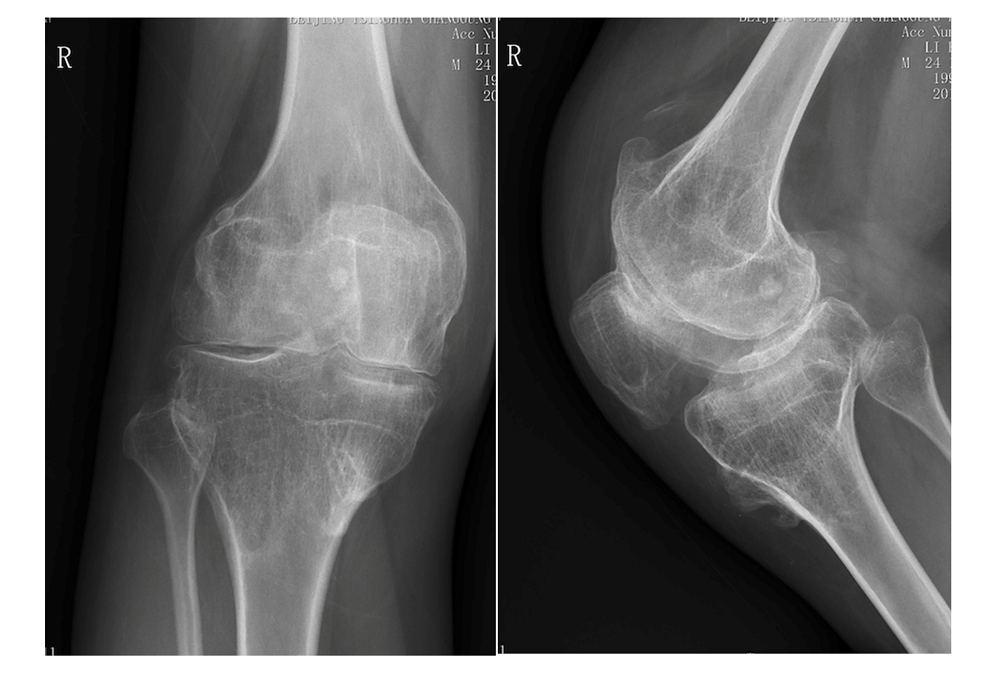

右膝关节X线片,骨质破坏严重